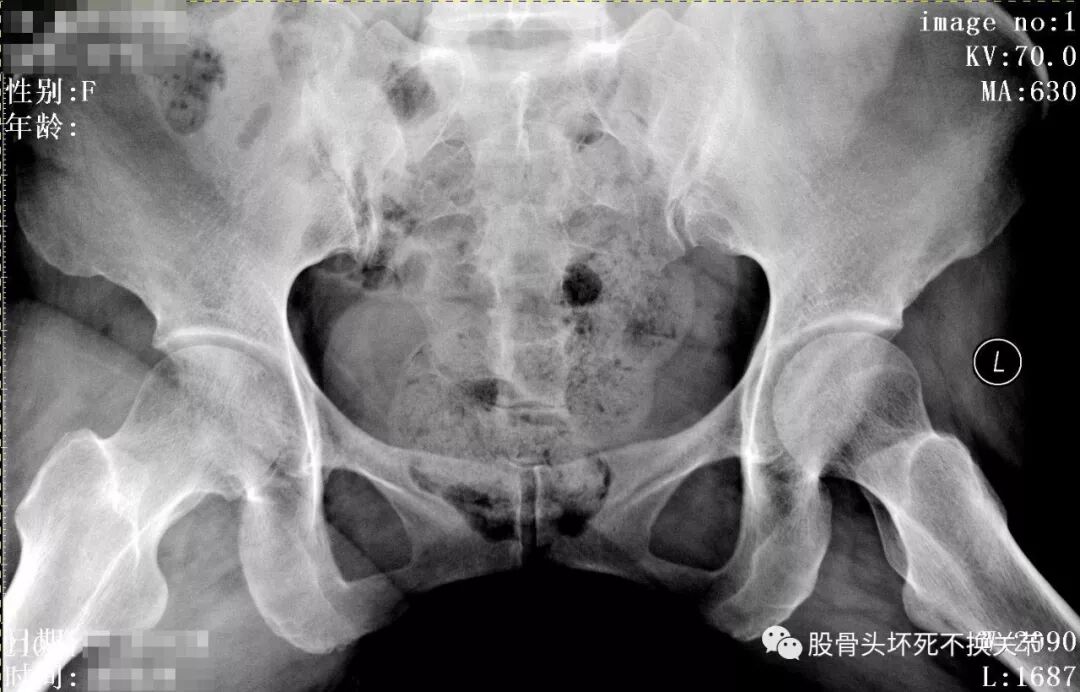

骨盆蛙位片

从这些歪斜的X线片子可以看到,双髋关节并无特殊表现,双侧骶髂关节似乎轻微硬化(对于42岁生过孩子的女性来讲,不首先考虑病理原因);仔细研判放大了的右髋关节正位、蛙位片,可发现股骨头边缘轮廓并不是特别光整,与对侧相比右侧股骨近端整体骨密度低于对侧,对于一个长期患病、缺乏活动的关节来讲,不足为道,很常见。

又过了半年,再次复查X线片:

股骨头除了骨密度更低之外,看不出来有特殊变化